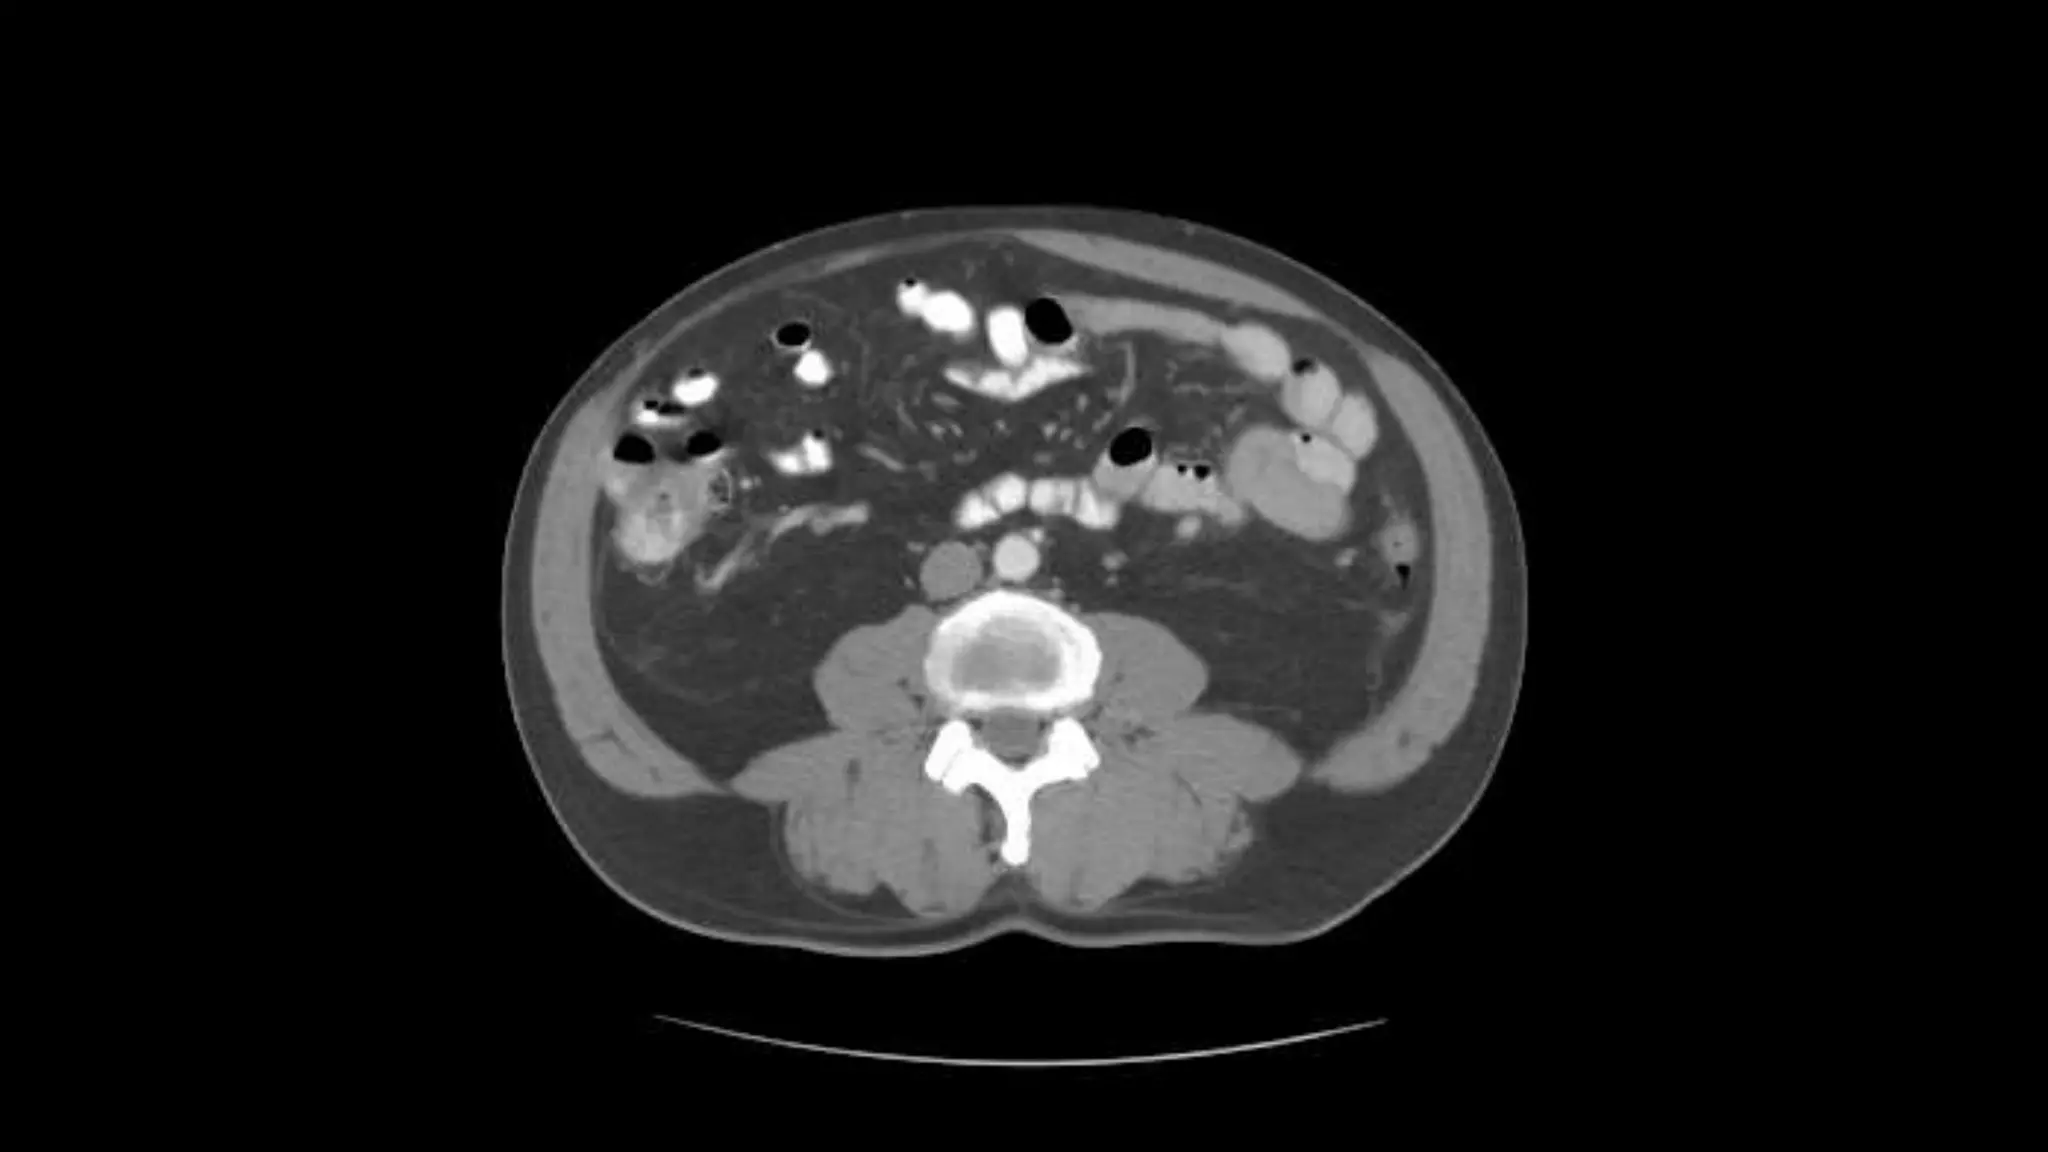

 In this sequence of images, we will label the abdominal vasculature.

The CT images are 5mm slices with soft tissue window settings. IV

and oral contrast have been administered which causes the vessels

and GI tract to appear hyperdense (white). Some images will contain

labels to assist with tracking the vessels.

 IMAGES ARE VIEWED AS LOOKING FROM THE FEET

RIGHT LEFT

Follow the IV contrast filled Aorta as we descend caudally. Branches and points

of interest will be noted.

Transverse Colon Small Bowell

Note inferior mesenteric artery emerging from aorta

Inferior mesenteric vein extends cephalad to join smv.